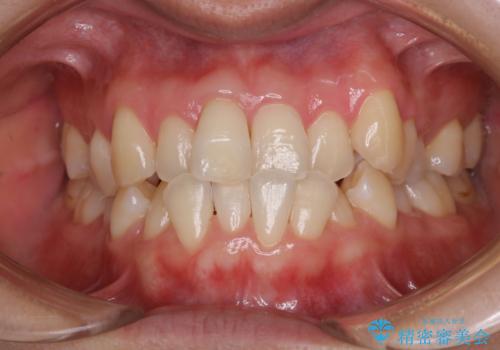

矯正治療が始まる前に歯磨きチェックとクリーニング

- 矯正治療がまもなくスタートするため、きれいにしたいのと歯磨きを上達したいとのことでした。染め出しをしての歯磨きチェック・指導とPMTC30分コースを行いました。

口腔内にはたくさんの細菌がいるため、ヌルヌルとしたプラーク(歯垢)が自然に歯の表面に付きます。

このプラーク(歯垢)にはたくさんの細菌が潜んでおり、虫歯や歯周病・口臭などの最大の原因です。そのため、毎日の歯磨きでプラーク(歯垢)をキレイに取り除くことが、健康な歯を保つためには欠かせません。

しかし、プラークは歯の色と似ているため、見ただけでは付着しているかどうかがハッキリとは分かりません。

染め出し液を使ってプラークを染め出すことにより、普段の歯みがきで磨き残している場所を目で確かめることができます。

日々の歯磨きを上達するには、まずどこが磨けていないか認識することが大切です。